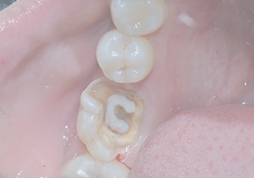

Deep Cavity

Pulp Inflammation